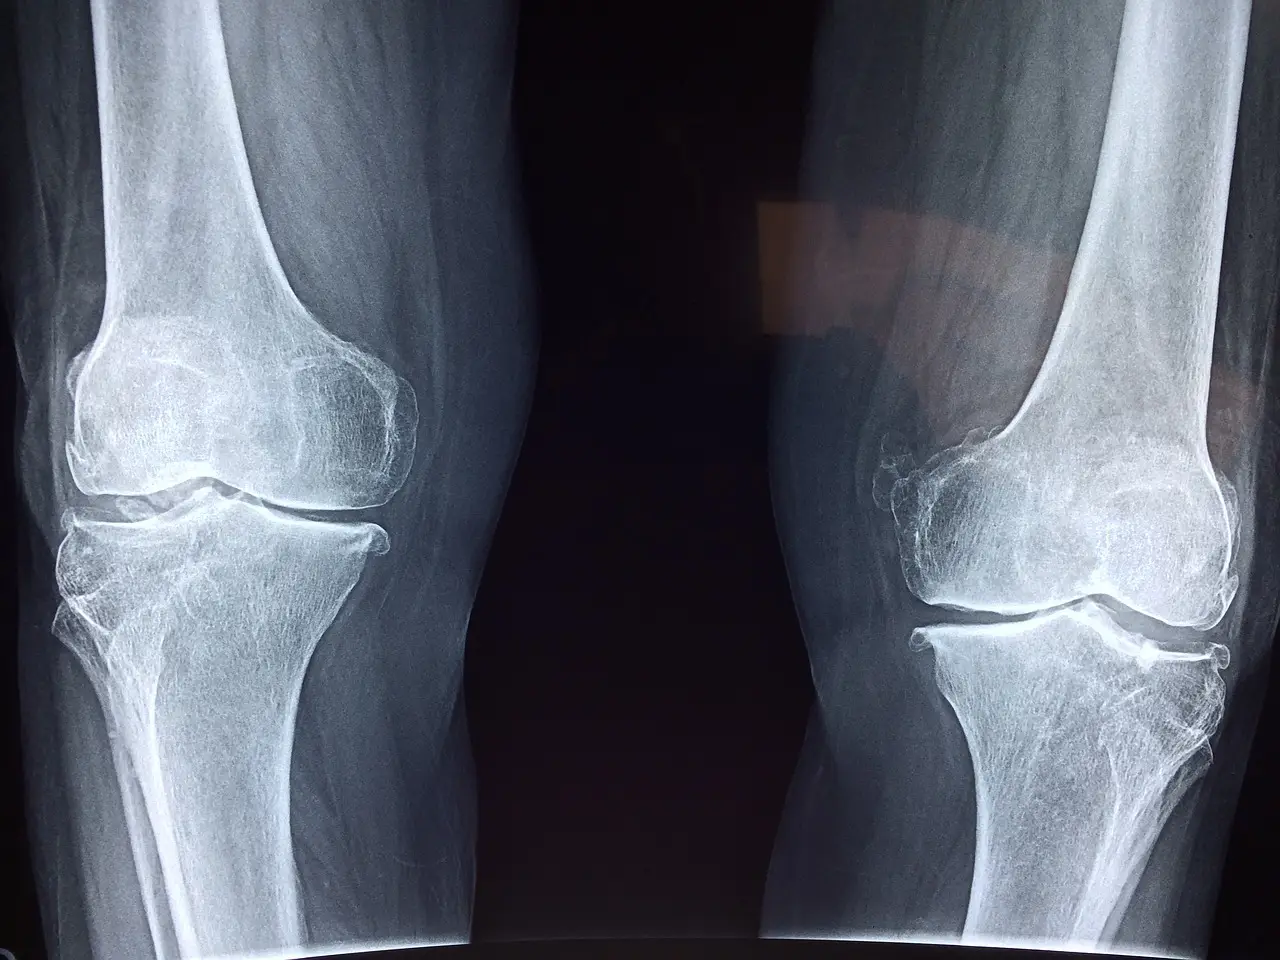

퇴행성 관절염이란 나이, 성별, 유전적 요소, 비만 등과 크게 관계없이 관절을 보호하는 연골이 손상되거나 퇴행성 변화로 관절을 이루는 뼈와 인대 등에 손상이 생겨 관절염과 통증이 발생하는 것을 말합니다.

건강보험심사평가원에 따르면 퇴행성 관절염은 현재 만성질병의 1위라고 합니다. 퇴행성 관절염은 자각을 하게 되었을 때 거의 늦은 경우가 대부분인데 이유는 혈관과 신경이 없어서 연골이 닳아 없어져서야 염증과 통증이 생기기 때문입니다. 혹시 모르니 대한슬관절학회에 접속하시어 무릎 관절염 여부를 한번 체크해 보시는 것을 추천드립니다.

무릎관절염 자가진단.xlsx0.09MB연골은 3mm 정도의 두께이며 재생이 불가능하기 때문에 미리 관리하는 습관을 가지시기 바랍니다.